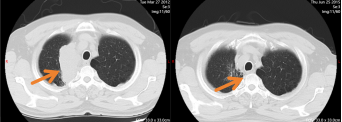

气管镜检查、病理活检等一系列检查后,张大叔被确诊为“右肺上叶小细胞癌局限期”。科室立即组织病例讨论,肿瘤内科、放疗科专家联合评估后,确定了同步放化疗的一线治疗方案——这是局限期小细胞肺癌最规范的诊疗路径。得益于平时硬朗的体质,张大叔对治疗的耐受性远超预期,没有出现严重的恶心、骨髓抑制等副反应。更令人振奋的是,仅完成2个周期化疗,复查CT便显示病灶明显缩小。那时再见到他,诊室里少了最初的沉默,他会主动说起“今天能多吃半碗饭”,紧锁的眉头渐渐舒展,眼神里的忐忑被平静取代。

2012年9月,全套治疗顺利结束。当张大叔看着新的CT报告上“未见明确肿瘤病灶”的结论时,终于露出了久违的笑容。此后数年随访中,病灶始终稳定,我们欣慰地判定:他的小细胞肺癌达到了临床治愈标准。

图1 第一次诊断肺癌,同步放化疗后右肺肿块消失